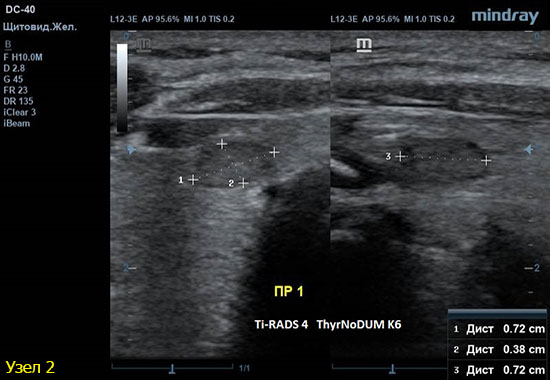

2) Узел у перешейка, не прорастает капсулу щитовидной железы (0 баллов), больше широкий чем высокий (0 баллов), не имеет кальцинатов (0 баллов), с ровным четким контуром (0 баллов), гипоэхогенный (2 балла), тканевой структуры (2 балла). Количество баллов 4, ACRTi-RADS4, ThyrNoDUMК6. Пункция не показана в связи с малым диаметром узла (более 1,5 см для Ti-RADS4), рекомендовано наблюдение.